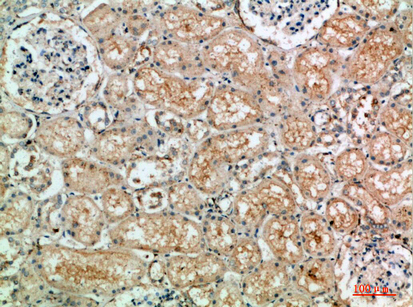

TLE1/2/3/4 (Transducin-Like Enhancer of Split 1/2/3/4) antibodies target members of the TLE protein family, which function as transcriptional corepressors involved in developmental regulation and oncogenesis. These proteins are homologs of Drosophila Groucho, sharing a conserved N-terminal Q domain and WD40 repeats for protein interactions. TLE proteins lack DNA-binding domains but modulate gene expression by interacting with transcription factors like HES1. RUNX, and TCF/LEF, thereby regulating Notch, Wnt, and other signaling pathways. Their roles span cell differentiation, apoptosis, and epigenetic regulation via histone deacetylase (HDAC) recruitment.

In diagnostics, TLE1 is a well-established immunohistochemical marker for synovial sarcoma, with nuclear staining aiding its distinction from other soft tissue tumors. TLE2 and TLE4 are less characterized but implicated in hematopoiesis and immune responses. TLE3 has gained attention in oncology for its potential association with chemotherapy response, particularly in gynecological cancers, though evidence remains inconclusive. Commercially available antibodies vary in specificity; cross-reactivity between TLE isoforms is a common challenge, necessitating careful validation in research and clinical settings. Recent studies also explore TLE dysregulation in neurodegenerative diseases, expanding their therapeutic relevance.